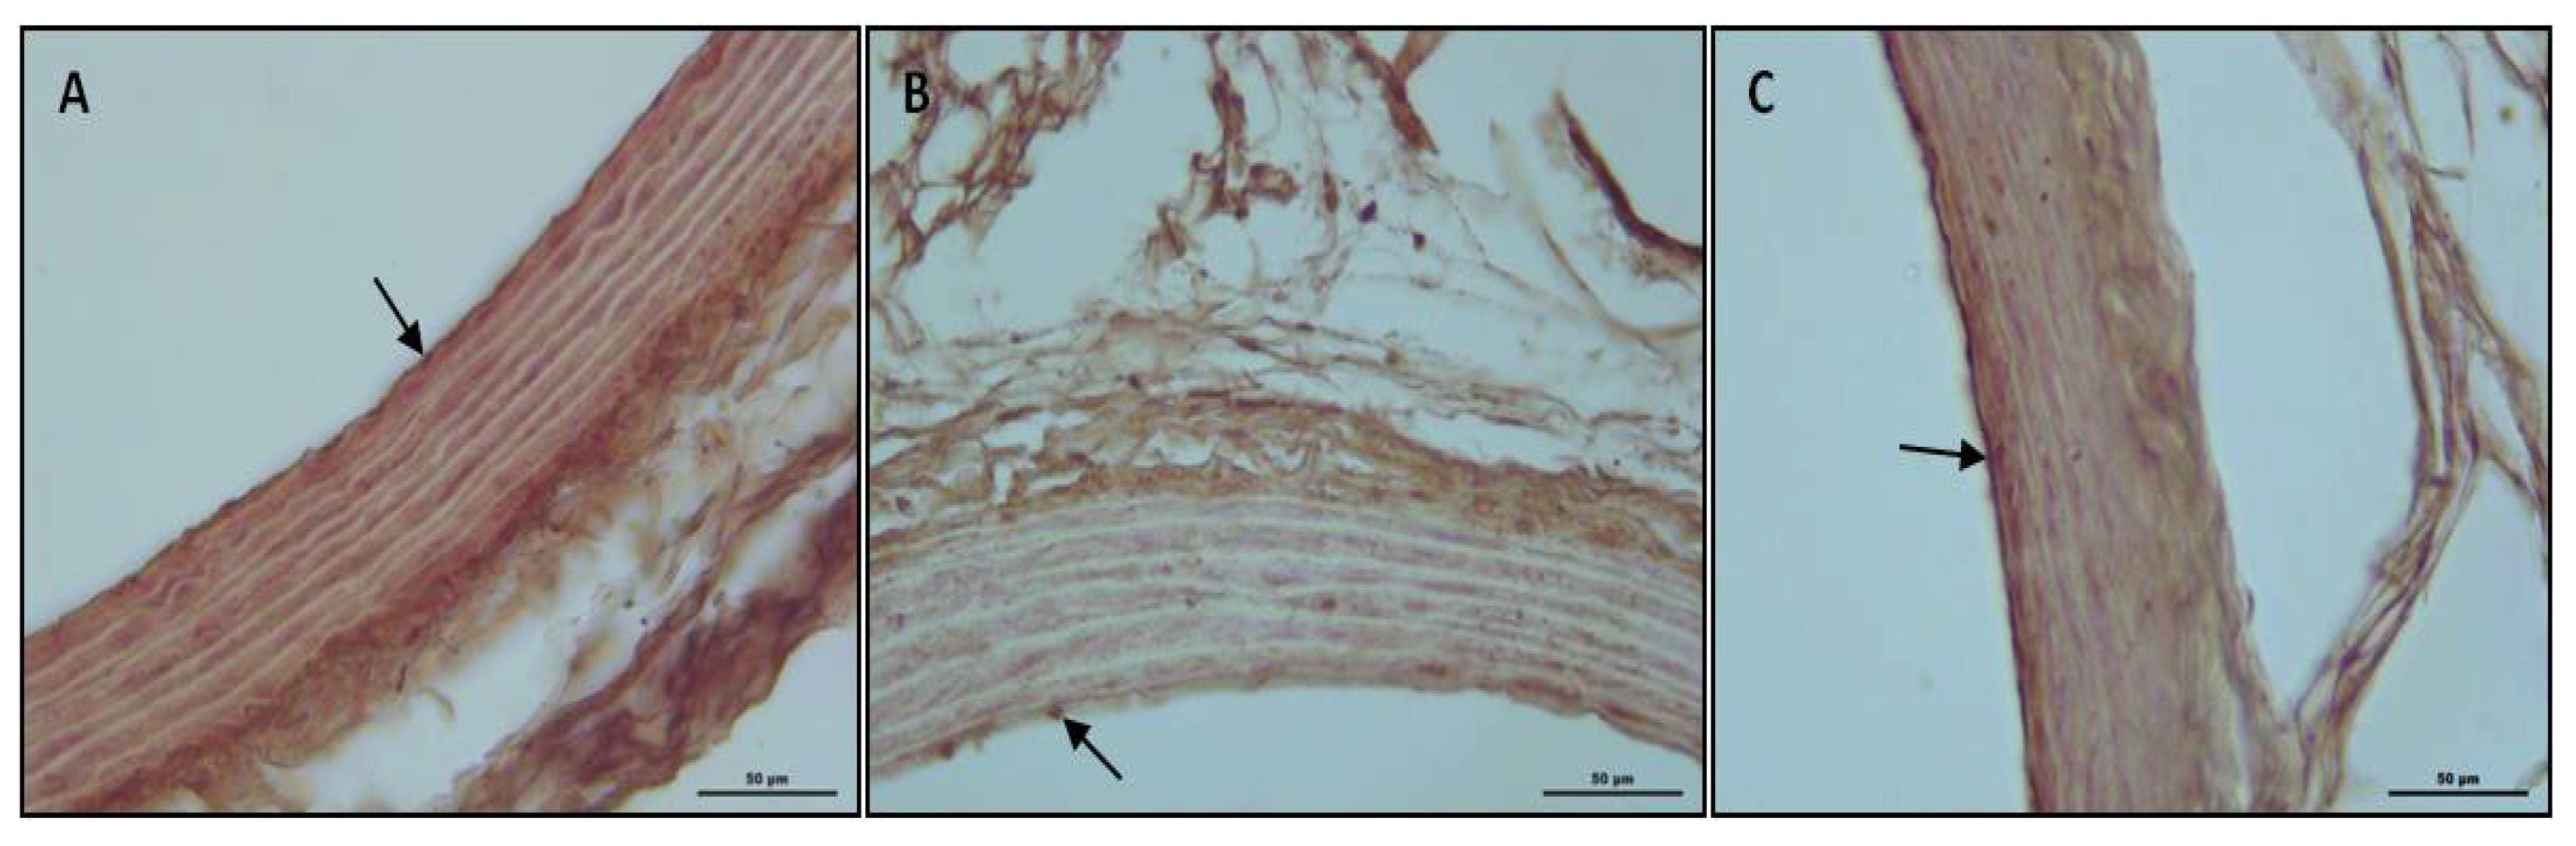

3.3. Etanercept Treatment Corrected Alterations of Endothelial Nitric Oxide Synthase (eNOS) Immunoreactivity

| Animal | Control | CD | CD + ETA |

|---|---|---|---|

| 1 2 | 2+ 3+ 2+ 2+ 3+ 2+ 2+ 2+ 2+ 1+ | 1+ 2+ 1+ 1+ 2+ 1+ 1+ 1+ 2+ 1+ | 2+ 2+ 3+ 2+ 2+ 1+ 2+ 2+ 3+ 3+ |

| 3 4 5 6 7 8 9 10 |